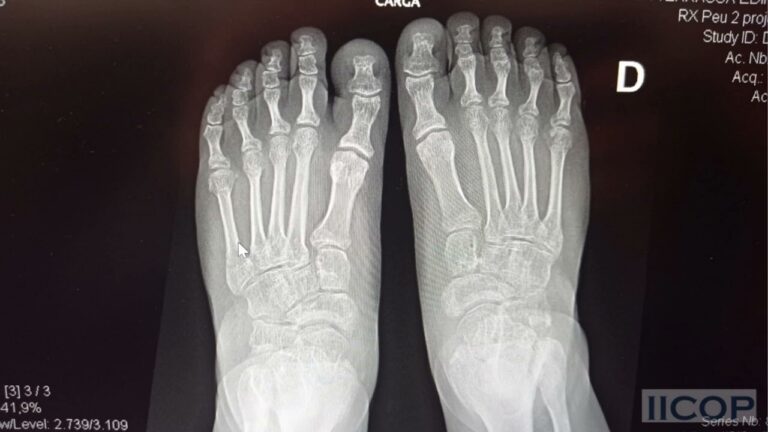

La luxación en el pie es una lesión dolorosa y debilitante que puede tener diversas causas, como traumatismos, deformidades congénitas o enfermedades como la artritis. Para su tratamiento, es crucial realizar un correcto diagnóstico, que puede incluir radiografías o resonancias magnéticas, y determinar el grado de luxación. Dependiendo de la gravedad, se pueden utilizar diferentes técnicas de reducción y se puede recomendar el uso de férulas o dispositivos ortopédicos. La rehabilitación y terapia fisioterapéutica son fundamentales para recuperar la movilidad y fortalecer la zona afectada.